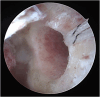

Graft-tunnel mismatch (GTM) is a known technical challenge that can occur with anterior cruciate ligament reconstruction when using a patellar tendon autograft. Two-incision anterior cruciate ligament reconstruction is a well-established technique with excellent outcomes and can serve as an excellent tool to prevent GTM. Traditionally, 2-incision femoral tunnel drilling has been performed using an over-the-top guide through a lateral incision, but more modern retrograde reamer guides can allow this to be done percutaneously. We detail how a minimally invasive 2-incision femoral tunnel drilling technique can be used in patients with patellar tendon lengths that are longer than average to avoid GTM.